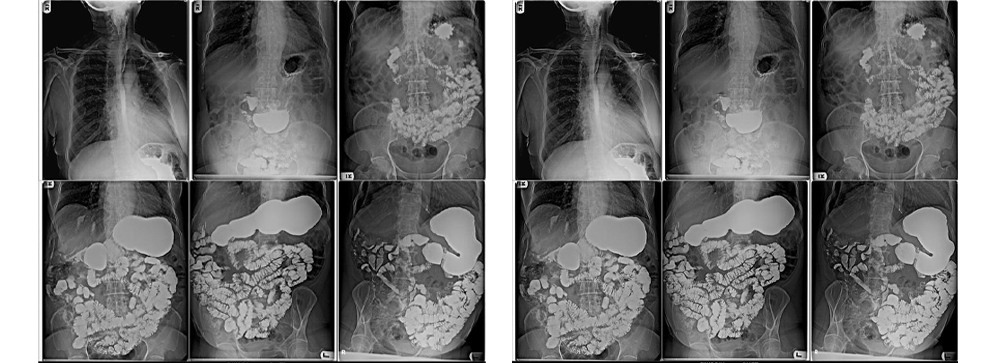

At Insight Diagnostics and Labs, we recognize that accurate diagnosis of digestive tract disorders plays a crucial role in delivering effective treatment and improving patients' quality of life. The Barium Meal Follow Through (BMFT) is a vital diagnostic imaging procedure designed to provide a detailed and dynamic visualization of the upper gastrointestinal tract, including the stomach and small intestine. This procedure involves the patient ingesting a barium sulfate contrast medium, which coats the lining of the digestive tract, allowing radiologists to track its passage using a series of X-ray images over time. The dynamic nature of BMFT offers a unique advantage by not only showing the anatomy but also assessing the motility and function of the digestive system.

A Barium Meal Follow Through (BMFT) is a detailed radiological examination that evaluates the anatomy and functionality of the stomach and small intestine. After swallowing a specially prepared barium sulfate suspension—a chalky, radiopaque contrast agent—the patient undergoes sequential X-rays taken at intervals to observe how the barium moves through the gastrointestinal tract. This real-time tracking helps identify a wide range of abnormalities such as ulcers, strictures (narrowing), tumors, areas of inflammation, and motility disorders that affect how food passes through the intestines.

At Insight Diagnostics and Labs, the BMFT is conducted using advanced digital radiography, a technology that offers continuous, live imaging with exceptional clarity. This method allows our radiologists to monitor both the shape and function of the digestive tract during the entire transit of barium. Unlike static images, this dynamic study can reveal subtle abnormalities that might otherwise be missed, providing a comprehensive picture of your digestive health. Our highly skilled radiologists analyze these images to detect even the smallest signs of disease or dysfunction, assisting your doctor in planning effective treatments.

The BMFT procedure begins with the patient drinking a barium sulfate contrast medium, which is typically a chalky white liquid with a mild taste. This contrast coats the lining of the stomach and intestines, making them visible on X-rays. Once ingested, the patient lies on the X-ray table, and a series of X-ray images are taken at regular intervals over one to three hours. Digital radiography allows continuous, live imaging, enabling the radiologist to track the barium’s progression and observe how the stomach and small bowel move and contract.

A barium swallow meal and follow through is a combined diagnostic procedure that examines the entire upper digestive tract. The test starts with swallowing a barium solution that coats the esophagus and stomach lining (barium swallow). This is followed by a “follow through” phase where the passage of barium through the small intestine is monitored via X-rays over time. This dual approach helps detect abnormalities in the esophagus, stomach, and small bowel, providing comprehensive insight into digestive health.